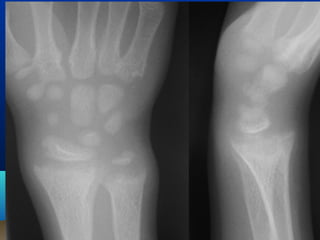

1. Widening of wrists and ankles

WWiiddeenniinngg ooff wwrriisstt jjooiinnttss

EExxttrreemmiittiieess 1. Wideningof wrists and ankles 2. Bending of long bones results in bow legs knock knees,(genu valgum) 3. Green stick fractures